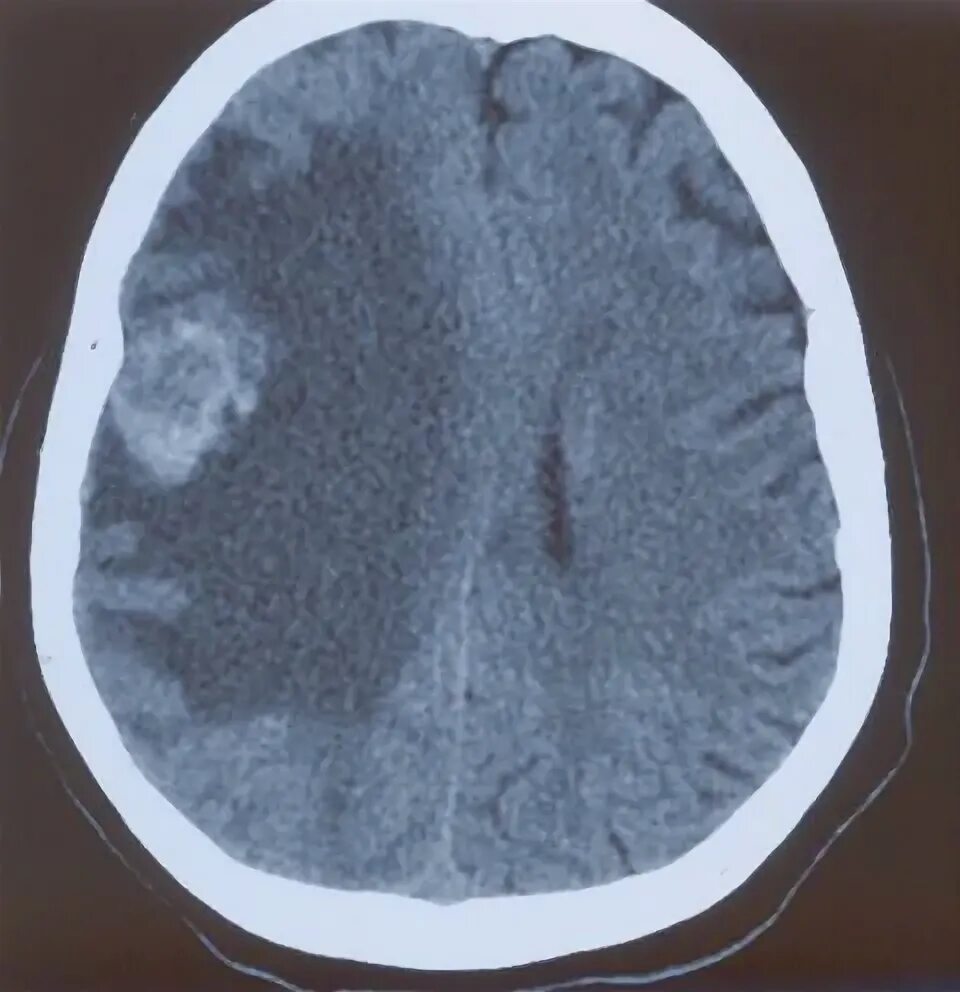

Перифокальный отек образования